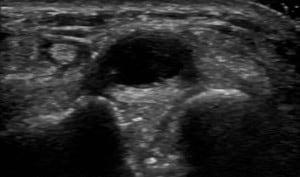

This in-depth case series webinar focuses on the ultrasound assessment of hand and wrist pathologies. Participants will explore a variety of clinical cases highlighting common conditions such as carpal tunnel syndrome, tendonitis, ligament injuries, fractures, and osteoarthritis. The session will provide practical insights into optimizing ultrasound imaging techniques for accurate diagnosis, along with tips for evaluating key structures like the flexor tendons, extensor tendons, carpal bones, and joints. Dynamic imaging techniques will also be discussed, enabling participants to better understand the role of ultrasound in guiding treatment and intervention for hand and wrist conditions. This case series is ideal for healthcare professionals looking to expand their musculoskeletal ultrasound expertise.